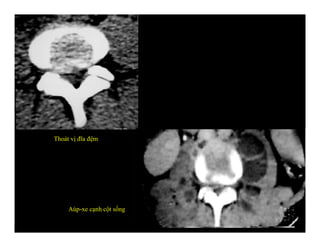

Thoát vị đĩa đệm

Aùp-xe cạnh cột sống

Thoát vị đĩađệm Aùp-xe cạnh cột sống